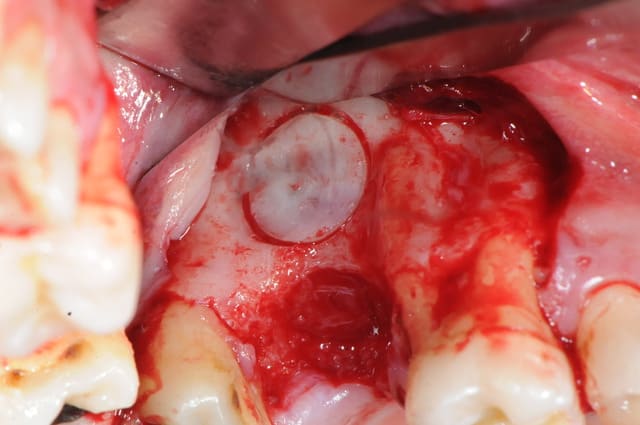

1&2 : réalisation à l'aide d'une tréphine de la fenêtre vestibulaire pour aller plus vite et surtout pour pouvoir réutiliser plus tard ce petit bloc osseux.

( vous verrez plus atrd à quoi ça sert)

3: fenêtre et CBS bien visibles

j'aurai aimé faire mon abord latéral plus haut, mais je vous rappel que l'on est au niveau de la 7 et que c'est difficile d'écarter les tissus.

(Rachel qui m'a gentiment assisté à beaucoup souffert de tétanisation musculo-palmaire multiple)

vous noterez tout de suite la différence de teinte entre un sinus sain et avec ici, un sinus hyper inflammatoire et infecté (une vraie cocotte-minute)

photo 1:

je cherche, je cherche, je soulève la membrane, et ..ohh! surprise!?

le dodo lé pas là !

mais ou est il ?

merde! ce con d'implant est parti faire un tout de poney sur sa selle turcique ou quoi ?? il est aller boire un coup avec les amygdales ?

bon, ben, si c'est pas resté sous le sinus, c'est que c'est dedans!

pas de pus, ni d'écoulement purulent pendant le soulèvement. comme il faut bien le trouver, je cherche sans ménager la membrane et ce qui devait se passer arriva; déchirure de la membrane.

pour une fois c'était presque voulu.

une fois percée, j'ai littéralement vidé le sinus du pus qu'il contenait avec l'aspiration.

2: comme il me fallait insérer la canule d'aspiration à travers l'opercule de la membrane pour vider le contenu sinusien, et comme l'aspiration venait me faire ch... à aspirer la membrane, j'ai décidé de la suturer sur le petit pont osseux pour la rendre plus stable.

3:

après de longues recherches et avec de la chance je l'ai enfin sorti. toutes la salle s'est écriée " ça y est le voilà!"

j'ai alors dit au patient; " félicitation, c'est un garçon!"